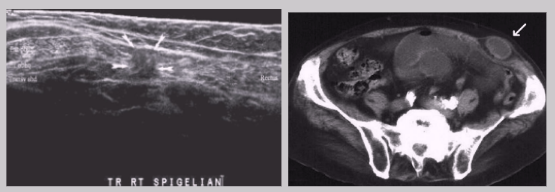

Spigelian hernia

Rare

Almost all occur at the inferior end of semicircular line, inferior to arcuate line where posterior sheath is absent

~ About 2 cm from the inguinal crease

High frequency of incarceration

Hard to diagnose because it occurs between the muscle or fascial layers of the wall rather than protruding through the wall